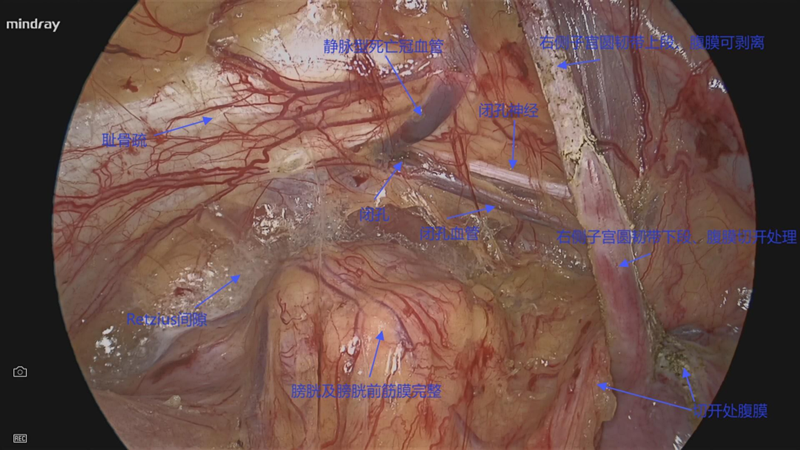

腹壁切口疝IPOM术中图片